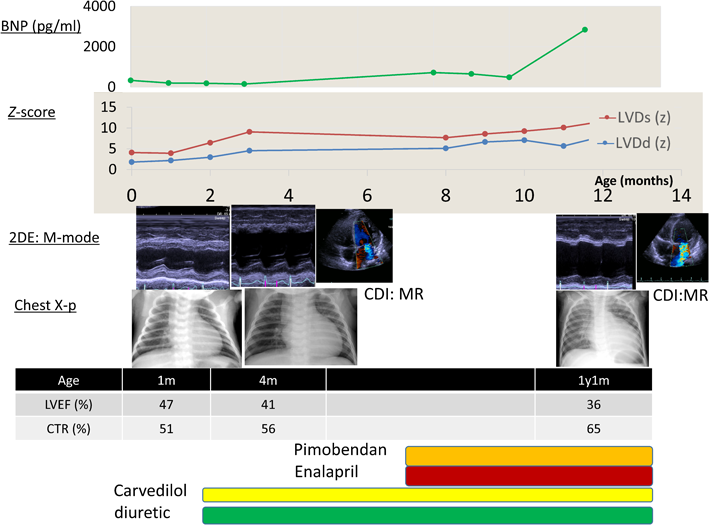

At 14 days of age, the infant presented with cyanosis while crying and was referred to our institution at 1 month of age. The patient was born to a 27-year-old healthy mother at term (40 weeks of gestation) and had a birth weight of 3,010 g. On physical examination, his weight was 3,200 g, which indicated poor weight gain, a likely reason for his poor sucking effort. His heart rate was measured at 120 bpm. Physical findings were significant for a II/VI systolic pansystolic murmur, with third sound and a 1-cm liver edge palpable on the right side. Initial blood evaluation revealed an elevated B-type natriuretic peptide (BNP) level (331.7 pg/mL). Electrocardiography revealed high R voltage from V4 to V6 and confirmed the LV hypertrophy. Two-dimensional (2D) echocardiography revealed the two-layer structure of the noncompacted (N) and compacted (C) layers and an N/C ratio of >2.0 at the lateral wall and apex (Fig. 1 (A1)). The Doppler echocardiography revealed that the flow within the deep intertrabecular recesses was in continuity with the LV cavity (Fig.1 (A2)). Moderate mitral valve regurgitation was also observed.

Fig. 1 Two-dimensional echocardiogram

A1: Two-dimensional echocardiogram showing the 2-layer structure of the noncompacted (N) and compacted (C) layers (N/C >2.0). A2: Color Doppler echocardiogram showing flow within the deep intertrabecular recesses (white arrow) in continuity with the left ventricular cavity.